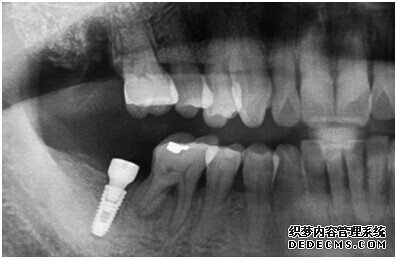

牙齿拍片初步检查

刘女士牙齿拍片初步检查

由CT片检查来看,刘女士口腔健康环境还是很好的,牙槽骨也适合种植牙的条件,而且由我们最后一颗牙是非常重要的,经过专家的建议和详细解释了原因之后,刘女士选择了美国百康种植牙。